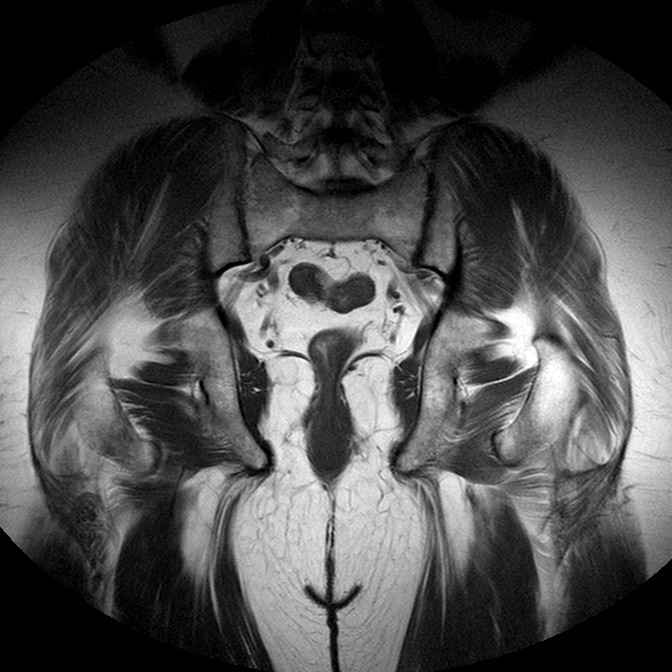

Esami: RMN BACINO

T1w TSE

Evidenti e simmetriche alterazioni osteofitosiche in regione coxo femorale con riduzione delle rime articolari. Degenerazione completa del cercine glenoideo. Non attuali segni di versamento articolare. Non segni di edema osseo che escludono attuale algodistrofia od osteonecrosi. Lieve e simmetrica riduzione del trofismo della muscolatura glutea.